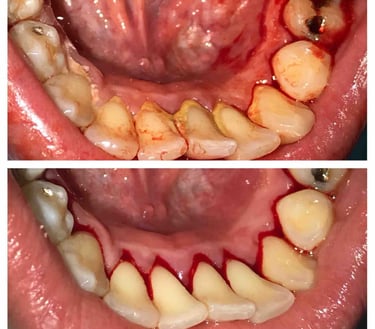

Treatment Results

Deep Cleaning

Deep cleaning, also known as scaling and root planing, is used to treat gum disease by removing plaque and bacteria from below the gum line and smoothing the tooth roots to help gums heal properly. Depending on the severity of the condition, the treatment may be completed in sections (such as half-mouth or quadrant visits) to ensure comfort and thorough care. After deep cleaning, ongoing periodontal maintenance visits every 3–4 months are essential to keep gum disease under control, as regular cleanings are not sufficient once periodontal issues are present.